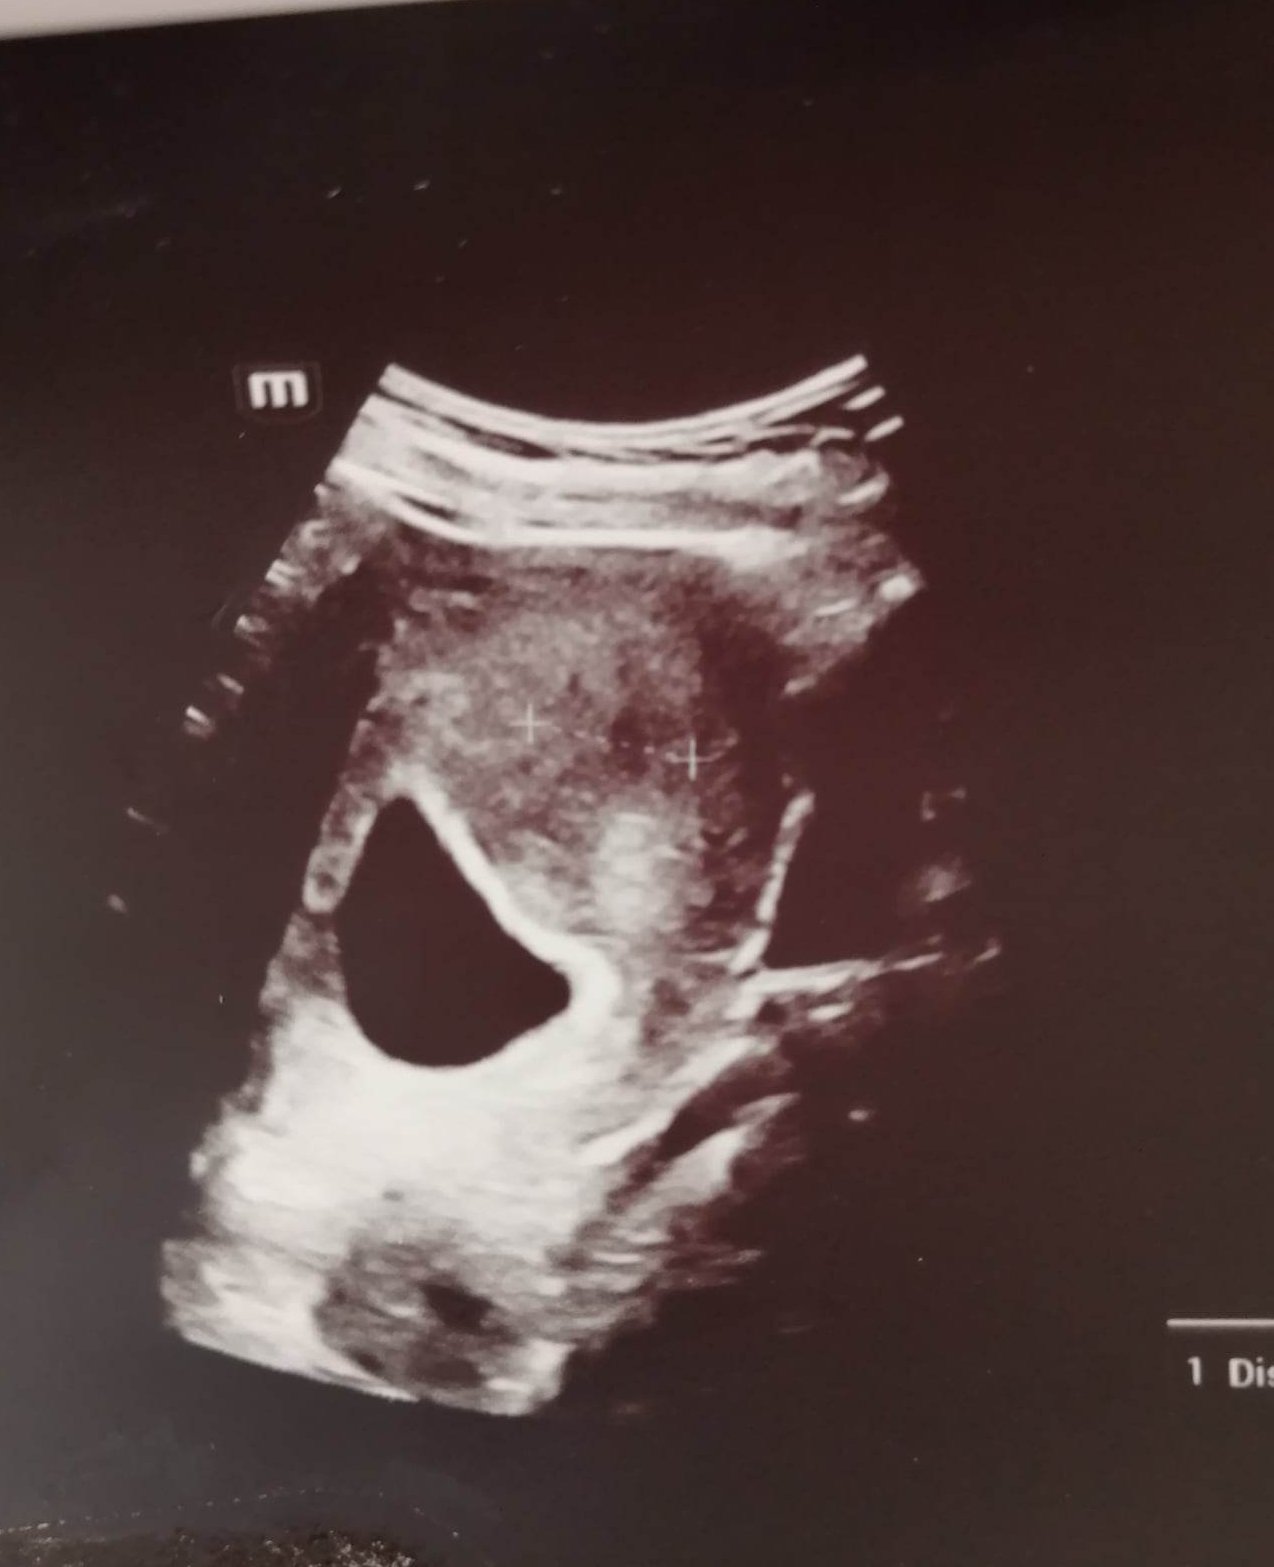

Записването на преглед зависи от индивидуалните обстоятелства, но обикновено лекарите препоръчват да изчакате поне 10 дни след закъснението, за да потвърдите бременността. В началото може да е твърде рано за откриване на пулсации, които обикновено се появяват около 8-та седмица. Ако забележите кървене или други симптоми, важно е да се консултирате с вашия лекар.

Жените с кафяво кървене трябва да се консултират с лекар, да избягват вдигане на тежко и да си почиват. Причините за кървенето могат да бъдат различни, включително нисък прогестерон, отлепване, полип, ранни признаци на шийката или неправилно развиващ се бременност. Важно е да се наблюдава дали има отлепване на плодния сак и да се извършат необходимите изследвания.